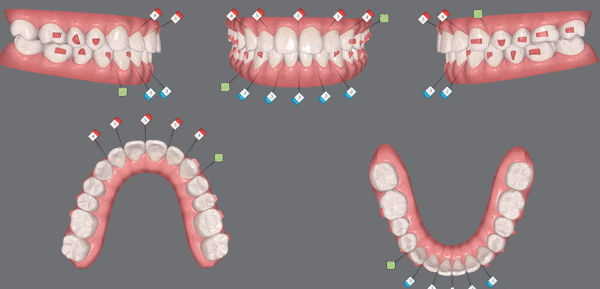

인비절라인 라이트로 단 28개의 장치를 통해 앞니의 뻐드러진 각도가

많이 개선되었습니다!

좁았던 악궁이 점점 확장되면서

뻐드러져 있던 앞니들이 안쪽으로 들어가고

맞닿고 있던 위아래 치아들이 제 위치를 찾았을 뿐만 아니라

입이 살짝 들어가 보이는 효과까지 얻을 수 있었습니다.

인비절라인을 통해 앞니의 접촉면을 최소화 하면서

치아의 심미적인 요소 뿐만 아니라 기능적인 요소 또한 개선시킬 수 있었어요. :)